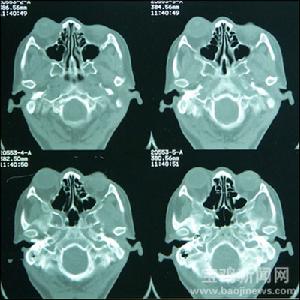

顱內腫瘤顱內腫瘤習稱腦瘤,分原發性與繼發性。原發性腦瘤來源於顱內各種組織成分如腦膜、腦組織、顱神經、腦血管、垂體腺與胚胎殘餘組織等。

顱內腫瘤的發生部位往往與腫瘤類型有明顯關係,膠質瘤好發於大腦半球,垂體瘤發生於鞍區、聽神經瘤發生於小腦橋腦角,血管網織細胞瘤發生於小腦豐球較多,小腦蚓部好發髓母細胞瘤等。